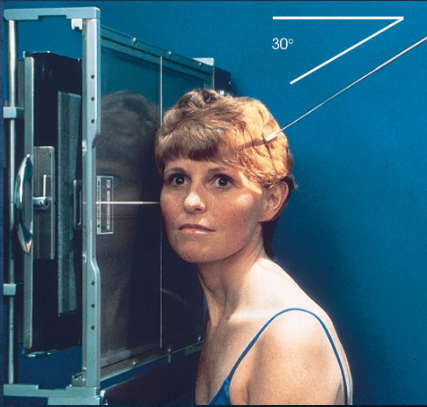

Axiolateral (modified Schuller) TMJs

patient position:

right or left lateral, both sides done for comparison

semiprone or upright

part position:

center ½ inch anterior to the EAM to the IR

head in true lateral

MSP parallel with IR

IPL perpendicular

one exposure with the mouth closed, and a second with the mouth open (if not contraindicated

respiration suspended

CR:

25-30 caudad

enters ½ inch anterior and 2 inches superior to upside EAM

collimation:

1 inch betond the anterior skin line, posteior and inferior to the TMJs

Axiolateral (modified Schuller) TMJs image criteria

TMJ with mouth open and closed

both sides done for comparison

TMJ anterior to EAM

closed mouth: condyle in mandibular fossa

open mouth: condule inferior to the articular tubercle